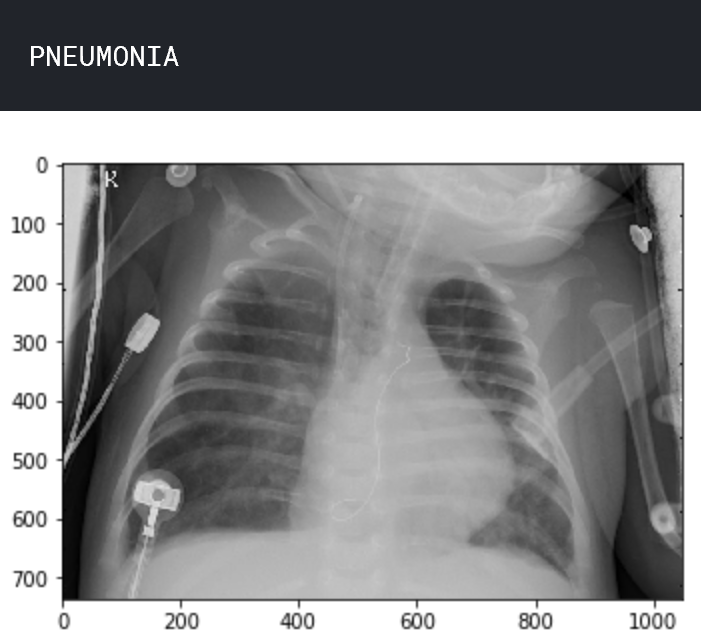

让我们了解数据。查看两个样本图像,一个处于正常状态,另一个处于肺炎状态。

img_name = 'person63_bacteria_306.jpeg'

img_pneumonia = load_img('../input/chest_xray/chest_xray/train/PNEUMONIA/ ' + img_name)

print('PNEUMONIA')

plt.imshow(img_pneumonia) plt.show()